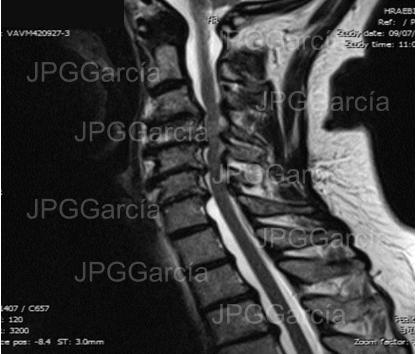

Estudio de resonancia magnética prequirúrgico

Estudio de resonancia magnética de columna cervical simple en el cual se observa un conducto cervical estrecho aunado a importantes cambios por imagen mielopáticos en el interior del tejido medular